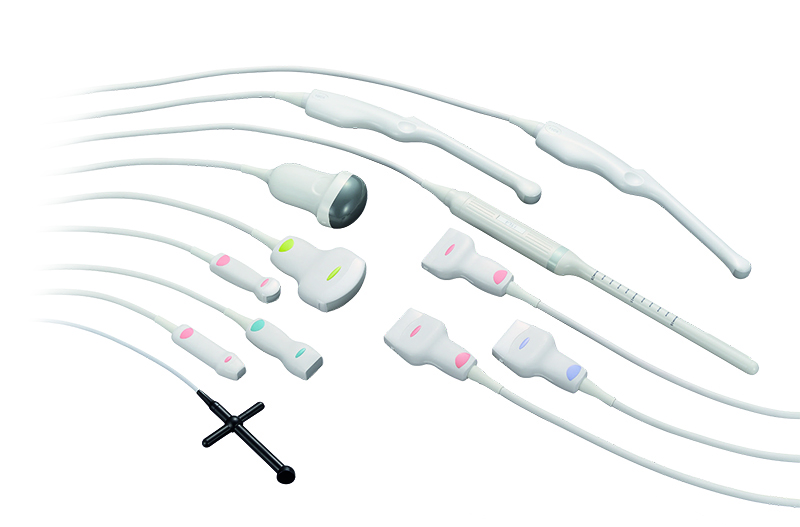

Підтримка широкої лінійки широкополосних мультифокальних датчиків з частотою до 14 MHz.

Абдомінальні дослідження

Поверхневі органи та малі структури

Сонна артерія

Скелетно-м'язова система

Кардіологія

Акушерство та гінекологія